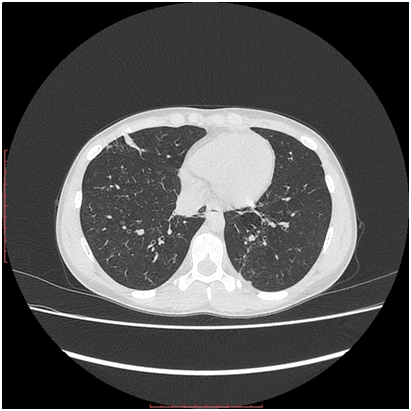

8. Chest CT: diffuse micro-focal centrilobular dissemination in the pulmonary tissue of both lings. Linear bridles with pleuropulmonary adhesions in S4 of the right ling (Figures 3 & 4) and in S8 of the left lung. Trachea and bronchi are viewed until sub-segmental, bronchial walls are thickened, with normally aerated lumens. Mediastinum and roots are well structured. Chest lymph nodes not enlarged. Diaphragm is normally situated, free fluid in the pleural cavities not seen. Pericardial layers are thin. Peripheral lymph nodes are not enlarged.

Figure 3 Chest CT. Diffuse micro-focal “ground-glass” changes in both lungs.

Figure 4 Chest CT. Diffuse micro-focal “ground-glass” changes in both lungs, and linear pleuropulmonary fibrosis in the middle lobe of the right lung.

And the last but not least, lung involvement in both cases was also relatively modest and torpid. In case 2 only chest CT demonstrated micro-focal “ground-glass” changes, characteristic for the early stage of the disease, or for the torpid course,13-17 while the plain chest X-ray examination failed to reveal any pathology features, even though the latest studies (both X-ray and CT) were performed 6 months after the disease onset. Such discrepancy between CT and Chest X-ray data is well described in the literature.13 In case 1 plain chest X-Ray also did not show any changes, despite severe iron deficient anemia, suggesting subclinical hemorrhage into alveolar spaces. Unfortunately we were not able to perform chest CT in that particular case, but we presume that diffuse “ground-glass” foci might be confirmed by CT, if it would be done.